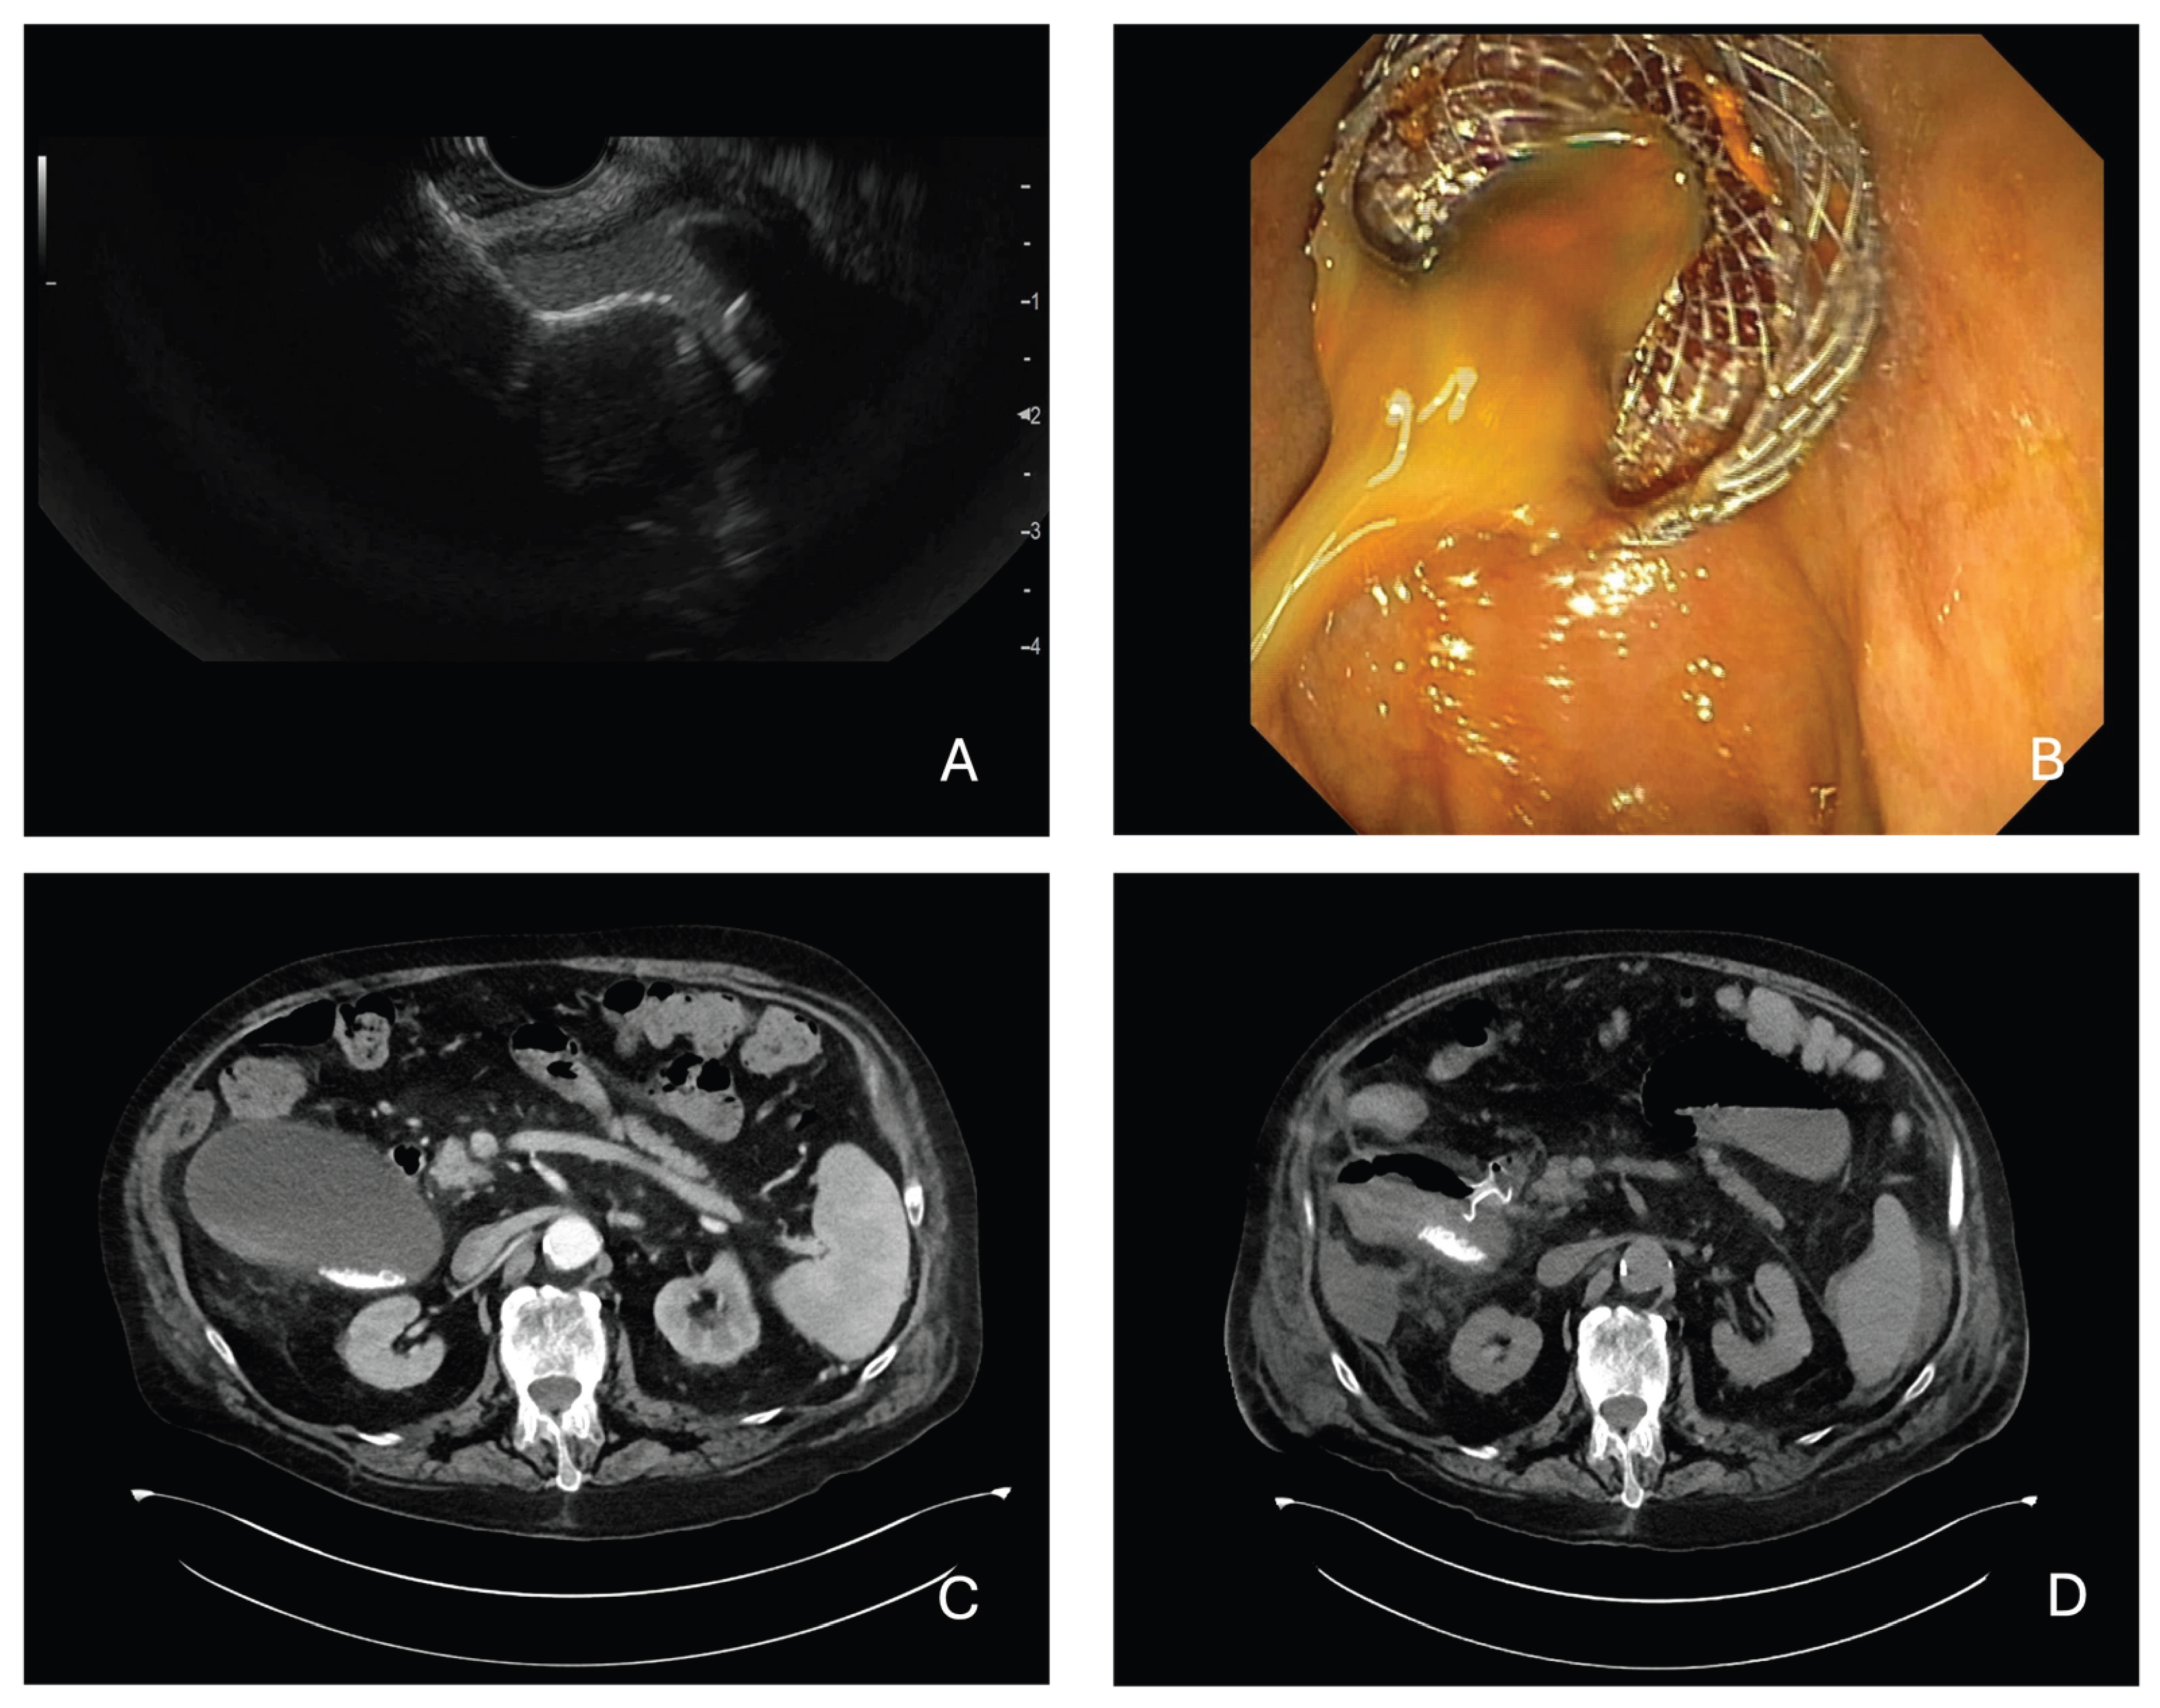

- Intervention: Endoscopic ultrasound-guided gallbladder drainage using LAMS;